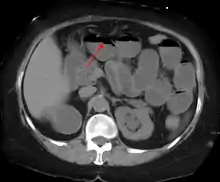

The main diagnostic tools are blood tests, X-rays of the abdomen, CT scanning, and ultrasound. If a mass is identified, biopsy may determine the nature of the mass.

Radiological signs of bowel obstruction include bowel distension and the presence of multiple (more than six) gas-fluid levels on supine and erect abdominal radiographs. Ultrasounds may be as useful as CT scanning to make the diagnosis.[13]

Contrast enema or small bowel series or CT scan can be used to define the level of obstruction, whether the obstruction is partial or complete, and to help define the cause of the obstruction. The appearance of water-soluble contrast in the cecum on an abdominal radiograph within 24 hours of it being given by mouth predicts resolution of an adhesive small bowel obstruction with sensitivity of 97% and specificity of 96%.[14]